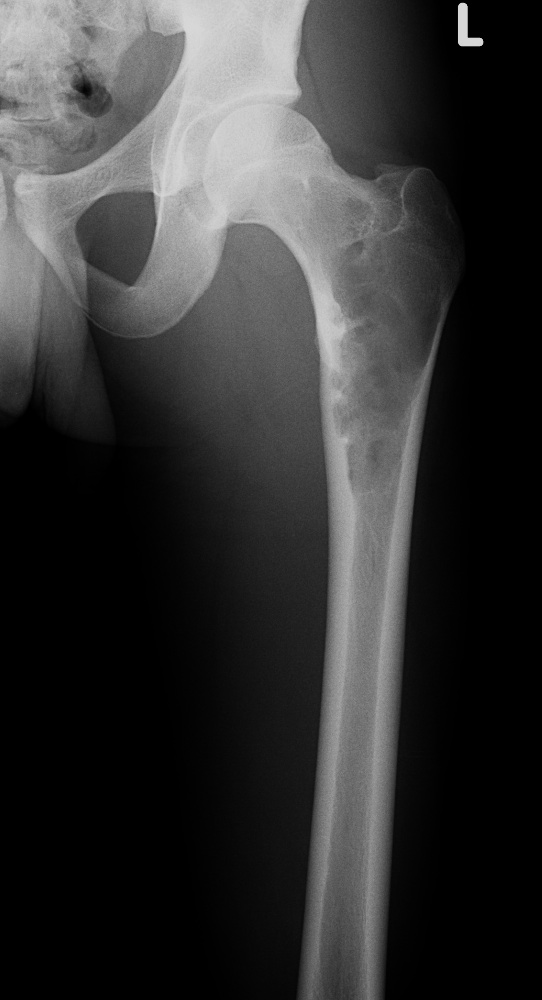

Молодая пациентка 23 лет. Травма в результате падения с высоты своего роста. Упала 2 дня назад доставлена к нам вот с такой картиной. Из анамнеза - боли беспокоят в течении полугода, постоянные. Никуда не обращалась. Уважаемое сообщество подскажите - ОБК?, Фиброзная дисплазия?, Киста?. Тактика ведения?. Девушка молодая!!!

На мой взгляд - это эссенциальная однокамерная киста или, скорее, аневризмальная.

А по пациентке:Обследования провели в легких чисто, лабораторно - без особенностей. Выполнили МРТ - костная киста, однокамерная. Оперирована - створчатая остеотомия, удаление кисты, костная пластика аутокостью с гребня подвздошной кости, остеосинтез DHS со сприральным клинком, створка фиксирована пластинами монокортикально.

Макроскопически - слизеподобное содержимое темно-бурого цвета, отдали на гистологию.